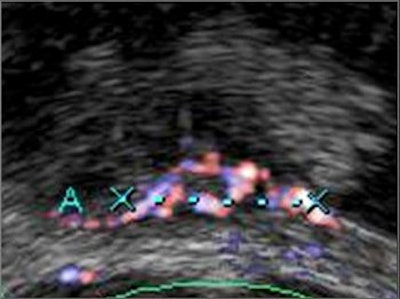

Freehand scanning was used for 3D data acquisition, and surface rendering and multiplanar reconstruction for 3D data analysis. Power Doppler ultrasound was used to differentiate the extent of infiltration. The criteria for staging were based on the vascularity of the tumor's basement. The gold standard was the histomorphology results.

| Power Doppler ultrasound criteria for staging vascularity of the tumor basement. Above, submucosal vessels; second, half muscle wall vascular. Below, whole muscle wall vascular; second image, few vessels in the perivesical walls; third image, massive flow in the perivesical fat. Images courtesy of Dr. Veronika Gazhonova, Russian President Medical Center and Russian State Medical University. |